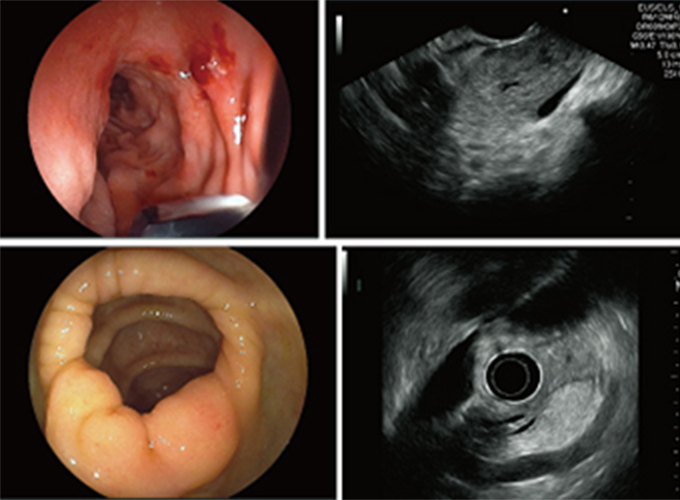

超音波内視鏡検査:EUS(Endoscopic Ultrasonography)

超音波内視鏡検査は、内視鏡装置(胃カメラ)の先端部分に超音波(エコー)を発生する器械が装着されており、消化管や周辺臓器の断面像を描出する検査です。 体外式超音波検査とは異なり、胃や腸の中の空気や脂肪が、画像化の妨げになることはありません。 超音波内視鏡検査はより詳細な画像情報が取得でき、病巣がどのくらいまで深く進展しているか、リンパ節転移や、周りの臓器への浸潤(しんじゅん)などについての詳細な情報を得ることができます。さらに、胃や十二指腸と隣接している胆嚢・胆管 ・膵臓なども、胃壁あるいは十二指腸を通して精密に調べることができます。 このような精密な画像検査は、手術における切除範囲の決定等、治療方針に重要な役割を果たします。 精密検査になりますので検査時間は通常の内視鏡検査と比べ長くなります。

超音波内視鏡下穿刺吸引法:EUS- FNA(Fine needle aspiration)

超音波内視鏡下穿刺吸引法(EUS-FNA)は、胃や十二指腸の消化管から(超音波内視鏡:EUS)で膵臓・胆道などの腫瘤を観察し、消化管内から針を刺して組織を採取する方法です。 直接組織を採取し評価することにより、診断や治療方針の決定に役立ちます。